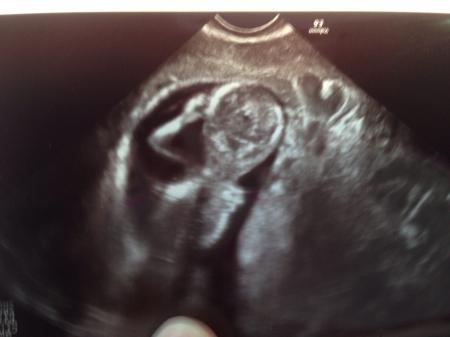

Hallo Mädels, Alles ist super :) Würmchen ist 5,5 cm groß und hat fleißig gezappelt. Wir sind total verliebt. Sofort als ich den Monitor gesehen hab, hatte ich das Gefühl, dass es ein Junge wird... bin gespannt. Bisher hatte ich das Gefühl, dass es ein Mädchen wird. Anbei 2 Fotos. Auf dem 1.Foto nuckelt es gerade; auf dem 2. kratzt es sich am Kopf :)

Bild zu Endlich Termin gehabt :) - Forum für Januar - Mamis